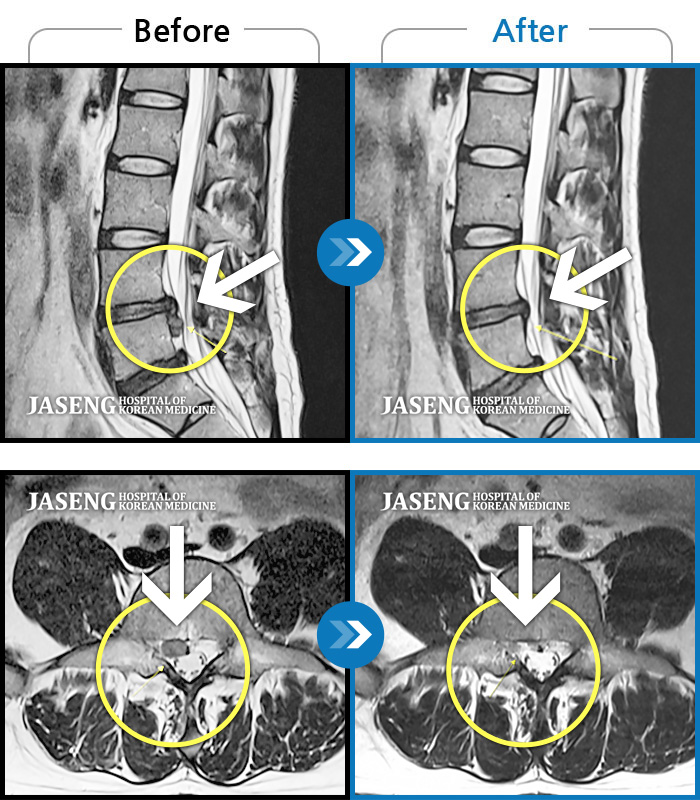

Before

After

환자에게 사전 동의를 받아 동일 조건에서 촬영되었습니다.

개인에 따라 치료 후 부작용이 발생할 수 있으니 의료진과 상담 후 치료를 진행하시기 바랍니다.

거동이 불가하여 내원하였고 야간통, 하지방사통, 하지저림

허리 통증 및 좌하지 방사통